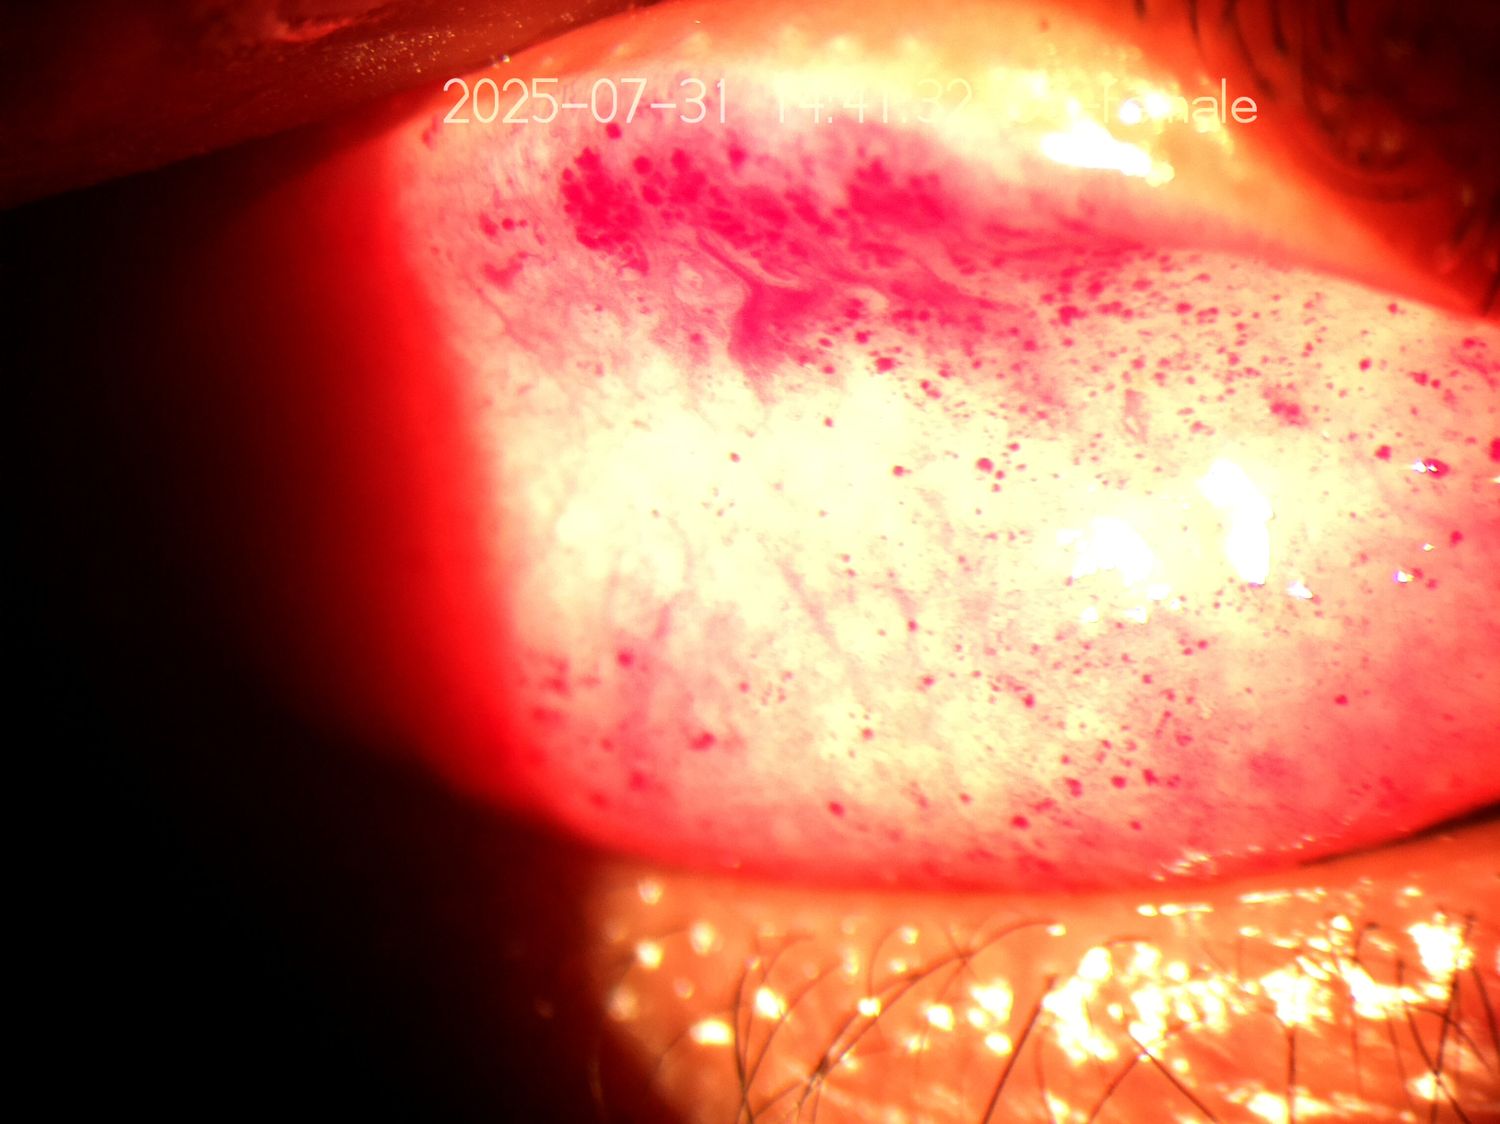

Ideal for tracking cataracts, pterygium, corneal ulcers, and medico-legal records. Improves patient understanding during counseling using clear visuals.

Image Gallery

Clear View Slit Lamp Imaging Solution Gallery